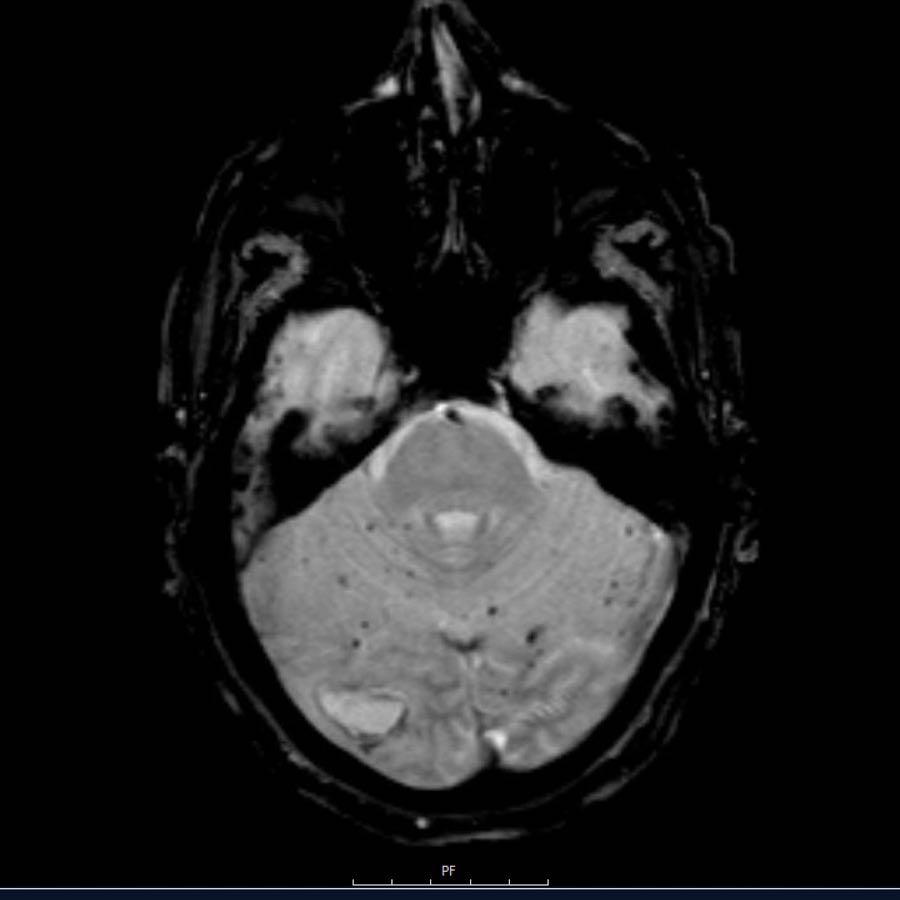

Bệnh nhân này nhập viện với xuất huyết tiểu não.

Các hình ảnh chuỗi xung gradient echo cho thấy nhiều vi xuất huyết.

Đây có thể là hậu quả của tăng huyết áp lâu năm do vị trí trung tâm của một số vi xuất huyết.